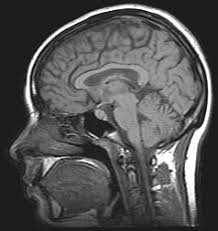

Idiopathic intracranial hypertension (iih) appears to be due to impaired cerebrospinal fluid (csf) absorption from the subarachnoid space across the arachnoid villi into the dural sinuses. Pseudotumor cerebri literally translates to false brain tumor. this term was used because symptoms of iih resemble those of brain tumors depsite no tumor being present. Tests for chronic intracranial hypertension. Common symptoms reported by people with idiopathic intracranial hypertension. Idiopathic intracranial hypertension (iih), often referred to as pseudotumor cerebri or benign intracranial hypertension, is a condition of unknown etiology that manifests with chronically elevated intracranial pressure (icp).

Pseudotumor cerebri literally translates to false brain tumor. this term was used because symptoms of iih resemble those of brain tumors depsite no tumor being present. In idiopathic intracranial hypertension (iih) there is raised pressure within the skull (raised intracranial pressure), which puts pressure on the brain. The doctor can figure out if your symptoms are related to iih or another condition. If doctors suspect idiopathic intracranial hypertension, they check the. Nord gratefully acknowledges bradley k. Iih produces signs and symptoms that result from the elevation of the icp. Idiopathic intracranial hypertension (iih), previously known as pseudotumor cerebri and benign intracranial hypertension, is a condition characterized by increased intracranial pressure (pressure around the brain) without a detectable cause. The primary problem is chronically elevated intracranial pressure (icp), and the most important neurologic manifestation is papilledema, which may lead to progressive. Idiopathic intracranial hypertension (iih) appears to be due to impaired cerebrospinal fluid (csf) absorption from the subarachnoid space across the arachnoid villi into the dural sinuses. It is a disorder defined by clinical criteria that include symptoms and signs isolated to those produced by increased intracranial pressure (eg, headache, papilledema, vision loss), elevated intracranial pressure with. It causes signs and symptoms of a brain tumor. Headaches, often at the back of your neck. Idiopathic intracranial hypertension (iih) is a disorder of raised intracranial pressure of unknown cause.

Idiopathic intracranial hypertension (iih) is also called pseudotumor cerebri. Idiopathic intracranial hypertension or iih is a neurologic disorder characterized by elevation of the intracranial pressure (icp). Sometimes doctors suspect it when they detect papilledema during a routine examination with an ophthalmoscope. What are the symptoms of idiopathic intracranial hypertension? Idiopathic intracranial hypertension, or pseudotumor cerebri, is a disorder that is caused by a buildup of pressure from too much cerebrospinal fluid in the idiopathic intracranial hypertension (iih) is a disorder related to high pressures of spinal fluid in the brain. It causes signs and symptoms of a brain tumor. Intracranial hypertension is a condition due to high pressure within the spaces that surround the brain and spinal cord. Idiopathic intracranial hypertension (iih), also known as pseudotumor cerebri, is a syndrome with signs and symptoms of increased intracranial pressure but where a causative mass or hydrocephalus is not identified.